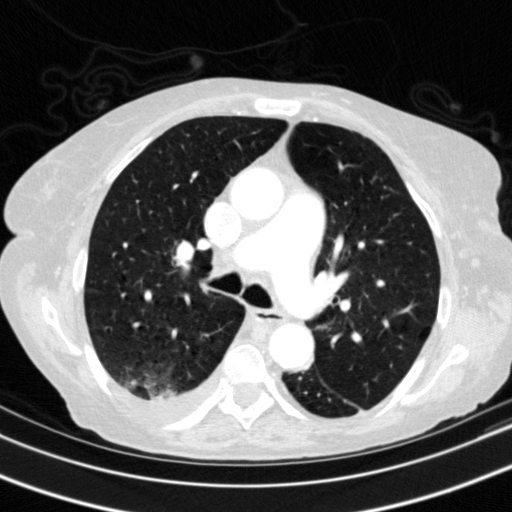

Reconstructed NATIVE CT scan (cycle consistency)

Full window (WL 1023.5, WW 4095 β†’ Low βˆ’1024, High +3071)

Lung window (WL -600, WW 1500 β†’ Low βˆ’1350, High +150)